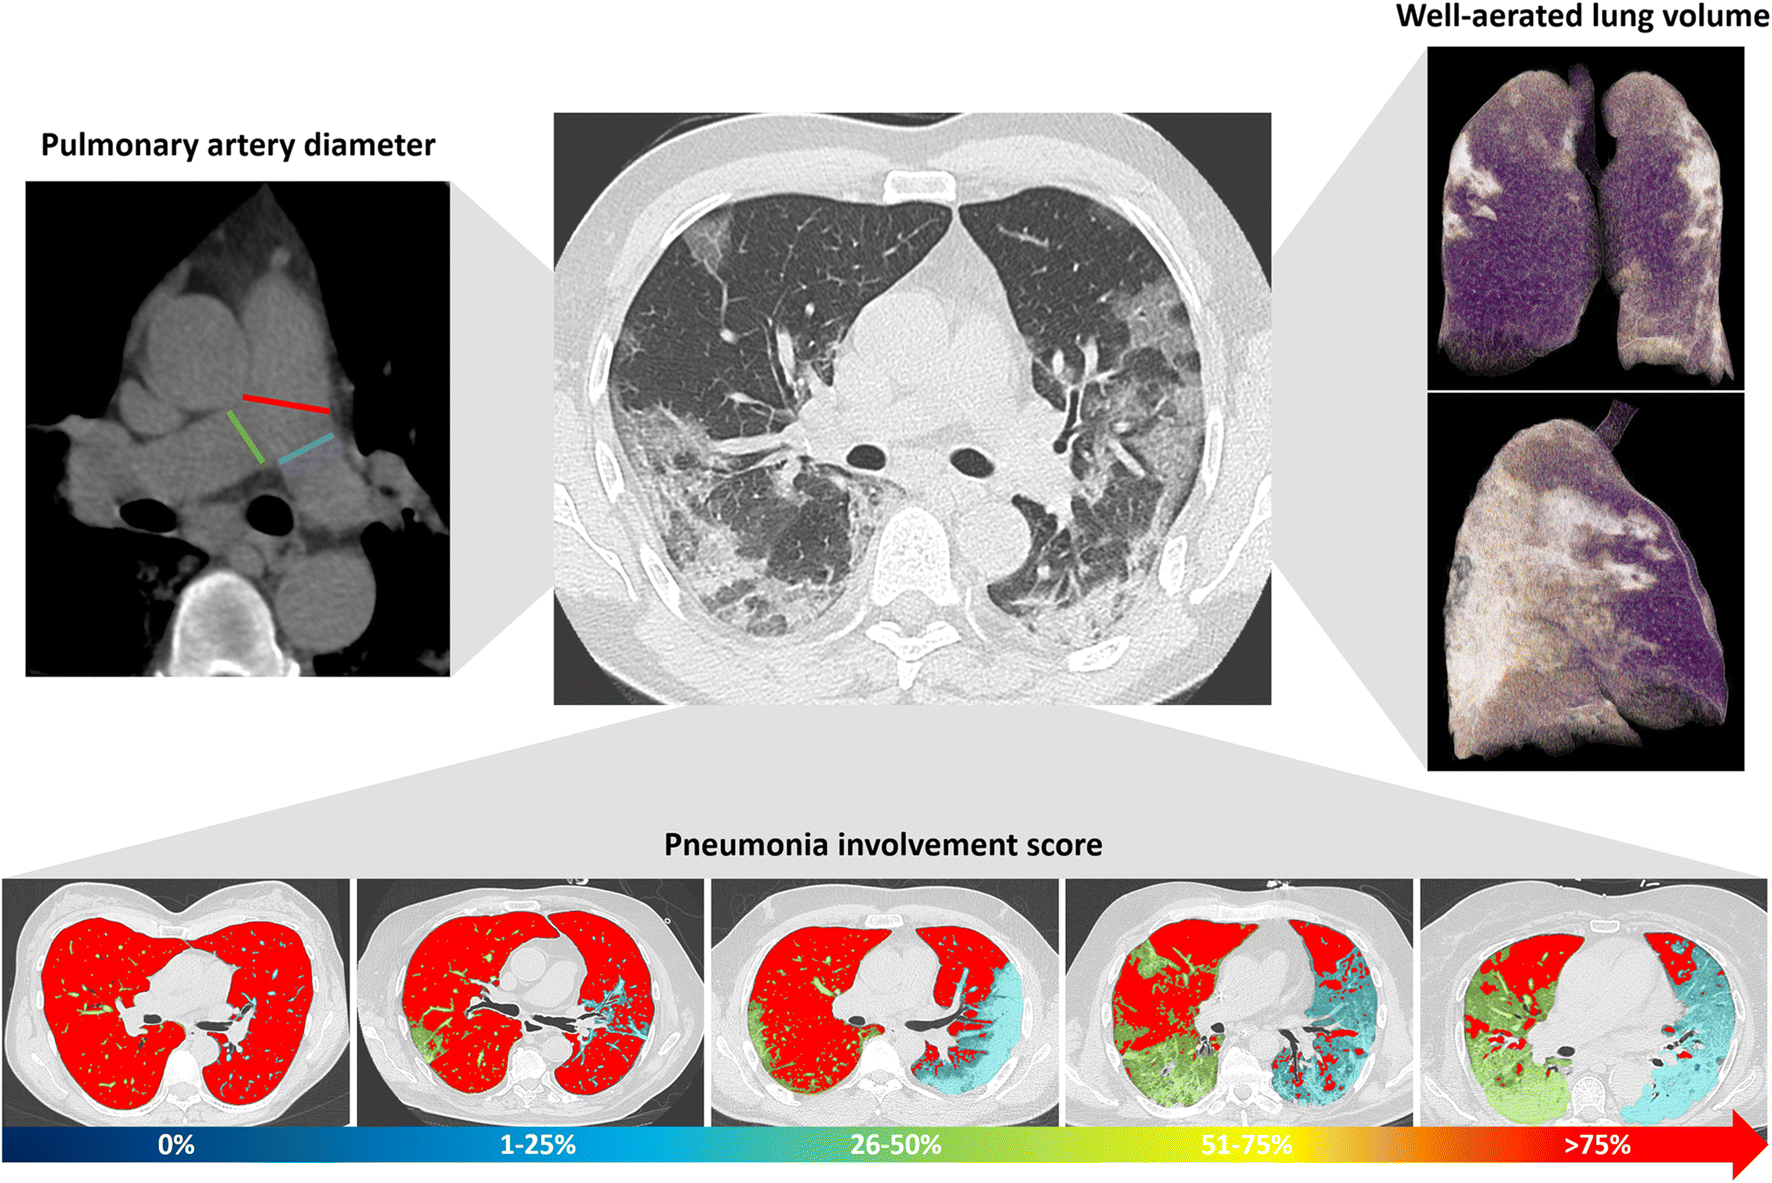

The analysis was performed by a radiologist with 9 years of experience in cardiothoracic imaging, blinded to all clinical data in order to reduce the possible bias in the analysis and to increase homogeneity and reliability of data. Parameters of lung involvement (residual respiratory lung reserve, pneumonia extension, and features) and pulmonary artery metrics were extracted (Fig. 2).

Fig. 2

Imaging parameters extracted from chest CT in COVID-19 patients. For each patient, the diameter of the main pulmonary artery (red line) was measured at the level of its bifurcation and the diameter of right and left pulmonary arteries at the level of their origin (green and blue lines, respectively) on the mediastinal window reconstruction (top left of the panel). Using dedicated software, well-aerated lung volume was automatically extracted (violet parenchyma in 3D lung volume rendering on the top right of the panel). Pneumonia involvement was scored from 0 to 4 (score 0: 0%; score 1: 1–25%; score 2: 26–50%; score 3: 51–75% score 4: > 75%); well-aerated lung parenchyma is displayed in red, and pneumonia in green for the right lung and in blue for the left lung (bottom of the panel)

Residual respiratory lung reserve was measured as well-aerated lung volume, quantified using automatic software (IntelliSpace Portal 8.0, Philips Medical Systems) based on a previously defined HU threshold value [17]. Pneumonia extension was scored in 0% (absent, score 0), 1–25% (minimal, score 1); 26–50% (mild, score 2); 51–75% (moderate, score 3); and > 75% (severe, score 4). Qualitative features of pneumonia were scored as follows: score 0 for absent pneumonia, score 1 for prevalent ground-glass opacities (GGOs), score 2 for prevalent consolidation, and score 3 for GGOs and consolidation equally represented. The metrics of pulmonary arteries included the measurement of the MPAD at the level of its bifurcation, of the left (LPAD) and of the right pulmonary artery diameter (RPAD) at their origin. MPAD was classified according to the severity classification system for the diagnosis and prognosis of PH [13] in four classes: normal (≤ 27 mm for females and ≤ 29 mm for males, according to the Framingham sex-specific normative values [16]); mild enlargement (from > 27 to < 31 mm for females and > 29 to < 31 mm for males); moderate enlargement (from ≥ 31 to 34 mm for both sexes), and severe enlargement (> 34 mm for both sexes). To assess inter-observer reliability, a second reader with 5 years of experience in cardiothoracic imaging, blinded to the measurements of the first reader, assessed MPAD and pneumonia score.